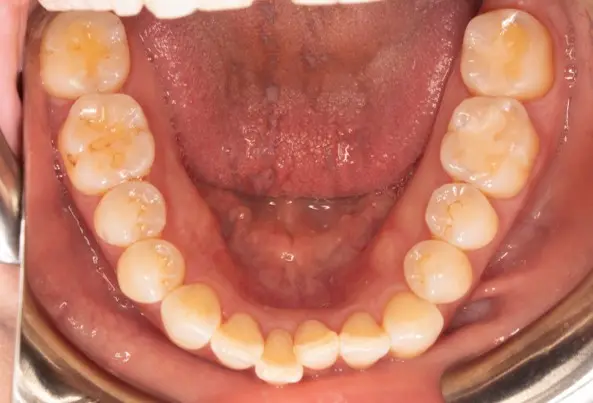

Before

After